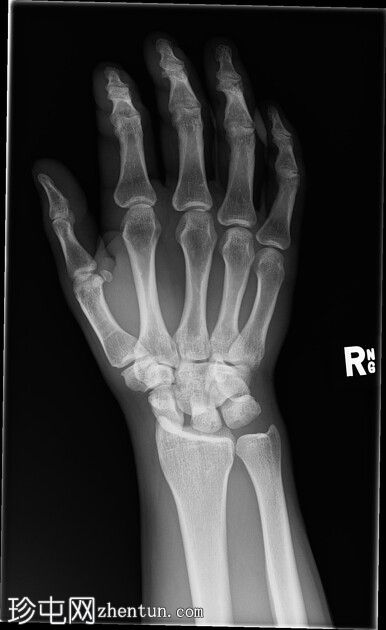

右腕

X光片

正面

斜位

侧面

前后位:舟月骨间隙增宽,月骨呈三角形。侧面显示头状骨与月骨背侧脱位,月骨与桡骨远端保持正常排列。符合月骨周围脱位的特征。无合并腕骨、桡骨或尺骨骨折。腕部软组织肿胀。